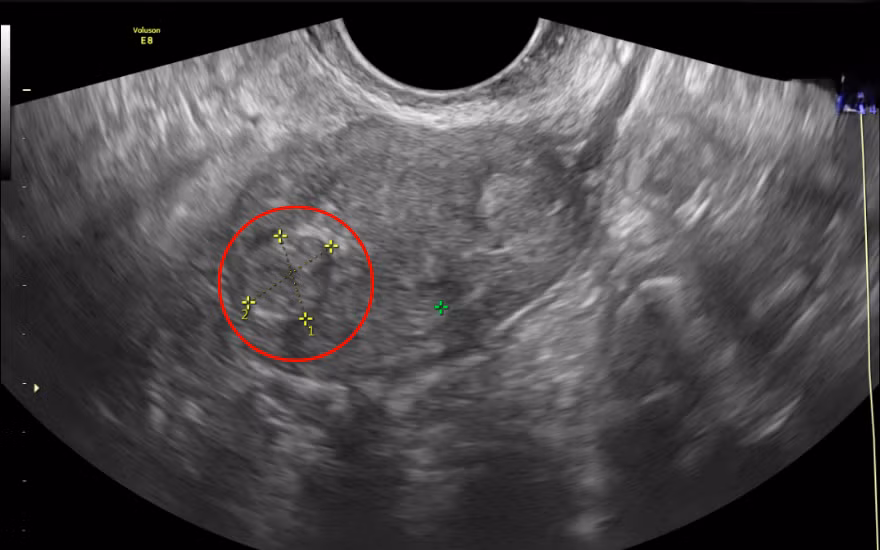

Ca phẫu thuật ngay lập tức được tiến hành. Trong hơn một giờ đồng hồ, các bác sĩ đã cắt bỏ hoàn toàn tử cung và phần phụ trái qua đường âm đạo, đồng thời tiến hành cố định lại vị trí bàng quang, tránh tình trạng tiểu khó và són tiểu kéo dài. Sau đó, toàn bộ thành trước và sau âm đạo được tái tạo nhằm củng cố hệ thống nâng đỡ sàn chậu, giúp hạn chế tình trạng sa sinh dục tái phát trong tương lai.

Ê-kíp phẫu thuật tỉ mỉ trong từng thao tác để đảm bảo xâm lấn tối thiểu vị trí tổn thương, bảo toàn tối đa các vùng lân cận - Ảnh BVCC